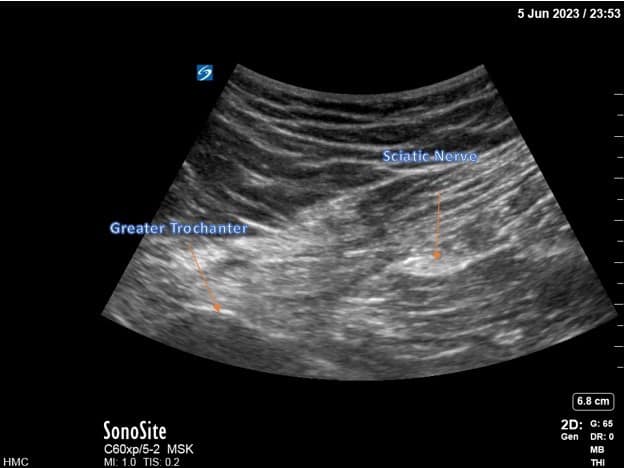

For infragluteal/midthigh sciatic placement, the patient is placed in the lateral position with the hip flexed and the residual limb supported by a stack of blankets. The ultrasound probe is placed transversely over the posterior thigh, and the sciatic nerve is identified (Figure 5). The positioning of the lead is more distal than a traditional infragluteal approach for patient comfort and to allow lead connection to the pulse generator. An in-plane technique is used (Figure 6). The steps for lead placement are the same as described above for femoral nerve lead placement. After both leads have been inserted, they are connected to the pulse generator secured on the anterolateral thigh (Figure 7).